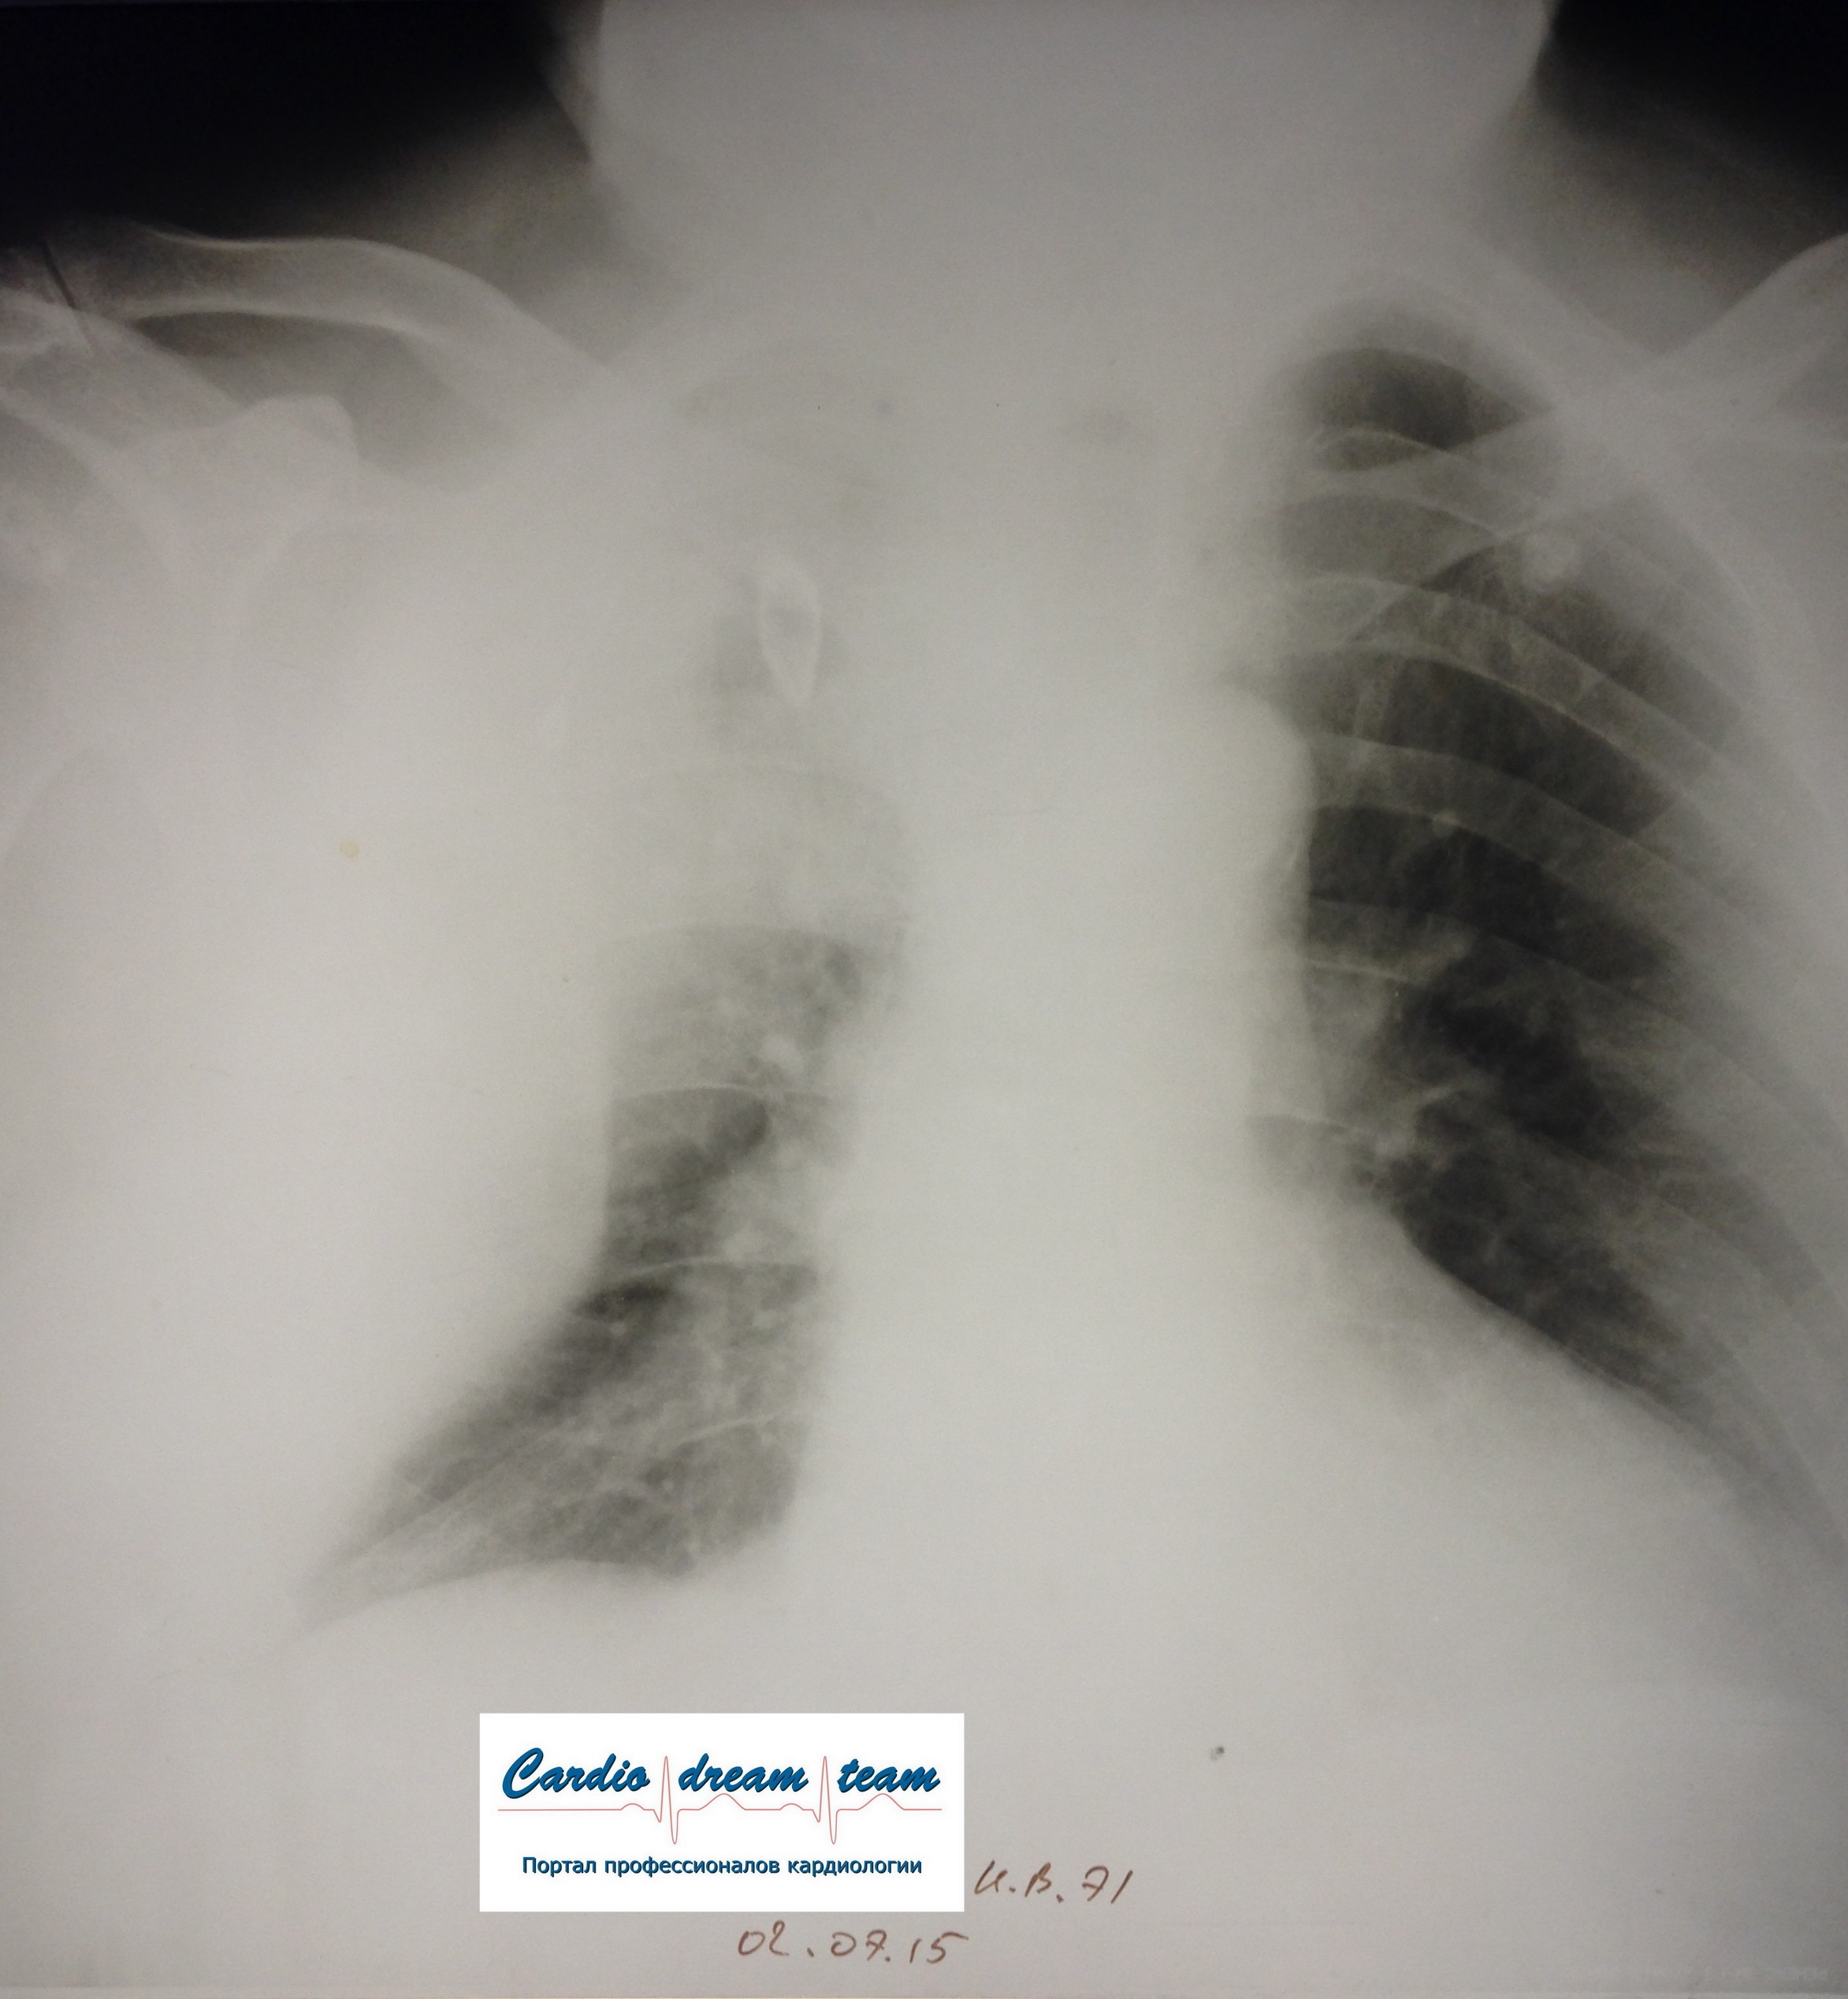

M, 71.

ТЭЛА. Есть увеличение правых отделов сердца. Давность около недели поэтому уже инфаркт пневмония слева с экссудативным плевритом, который виден очень хорошо.